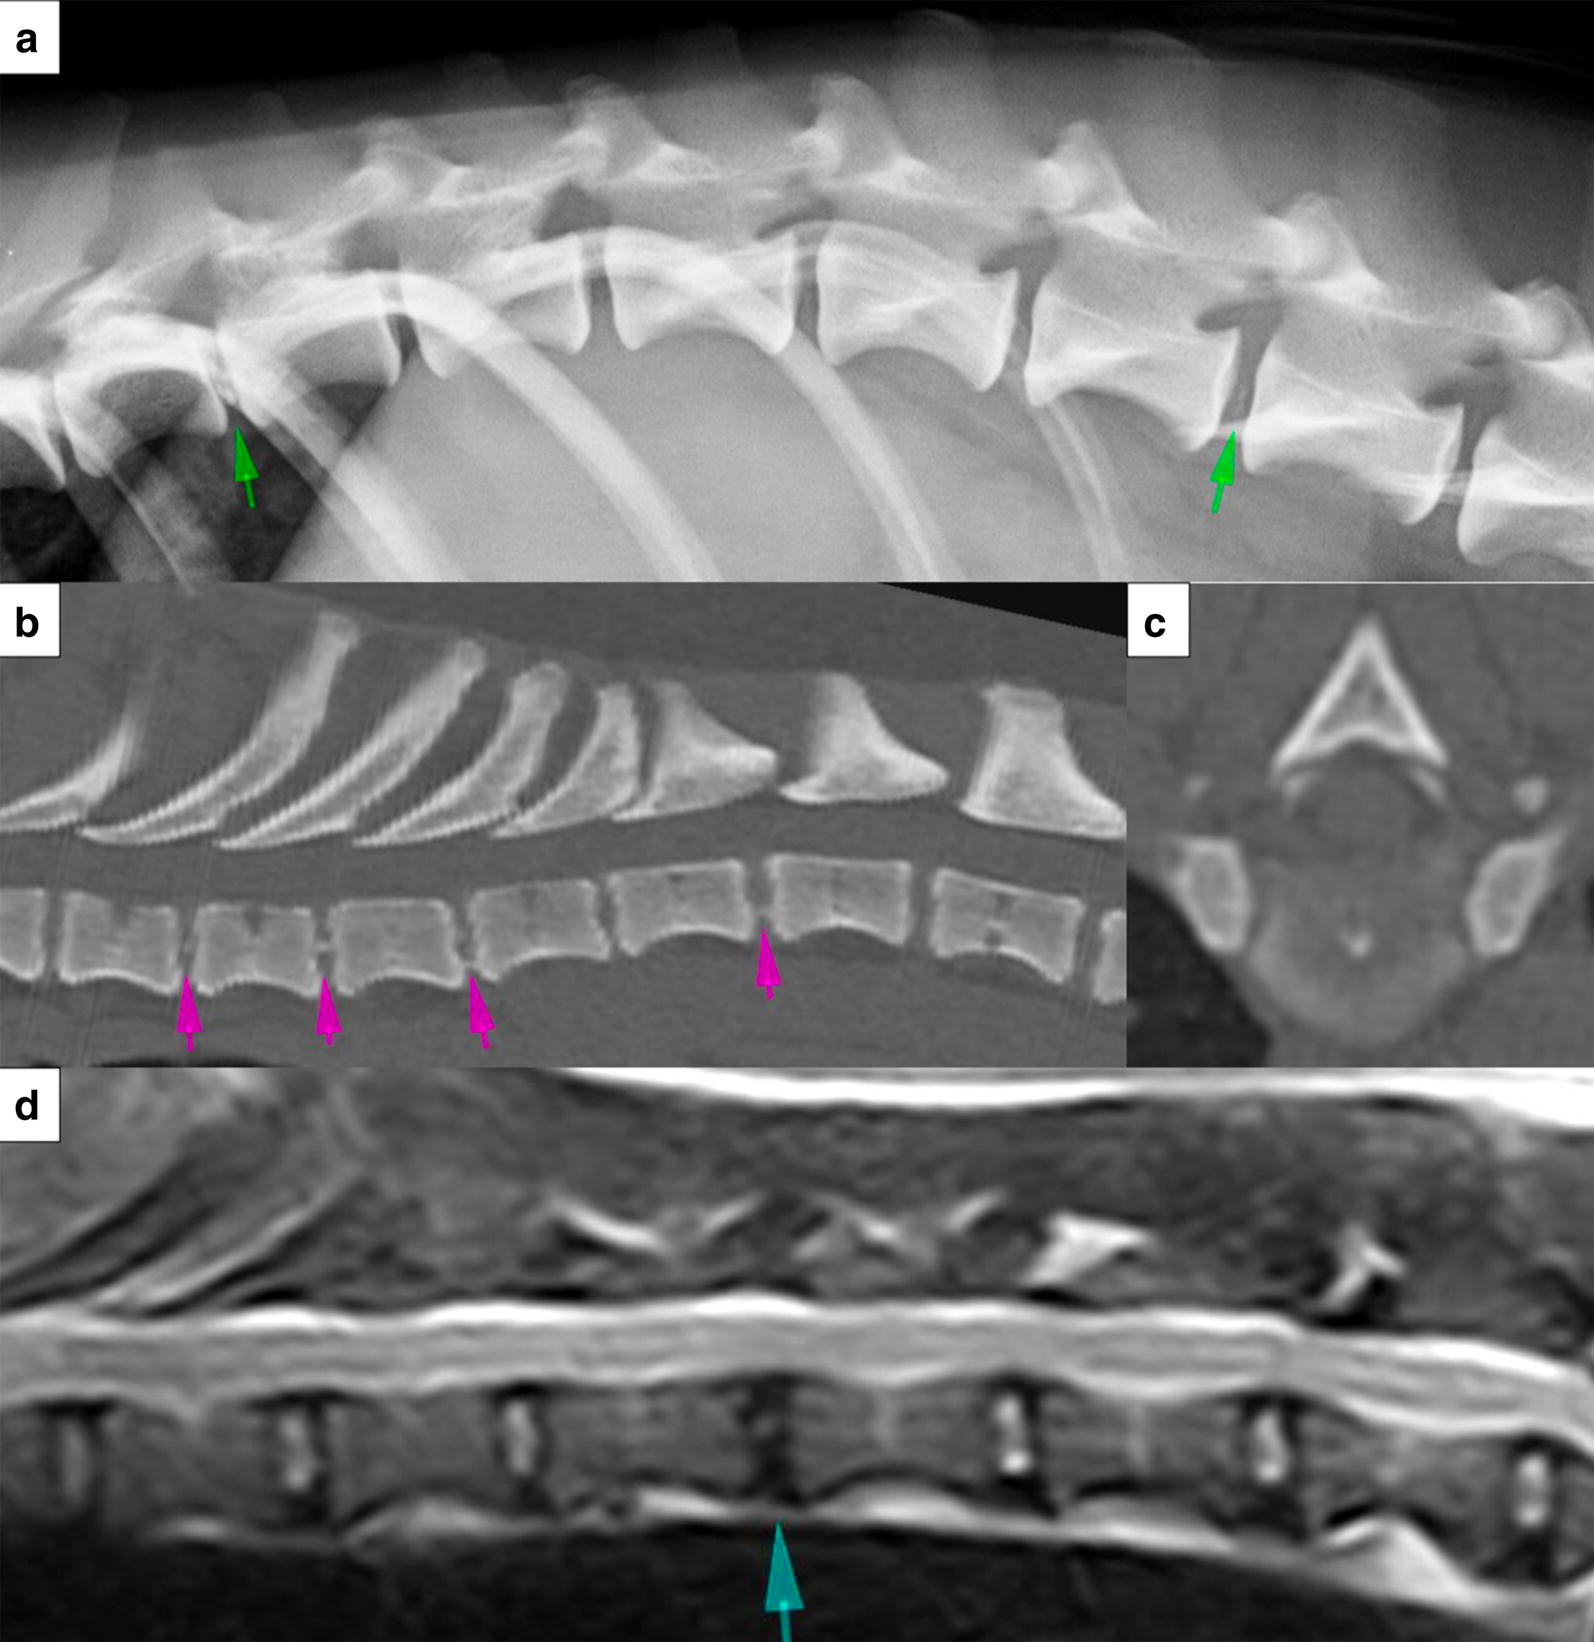

Fig. 1.

Example radiographic (a), CT (b, c) and MR (d) images obtained for intervertebral disc (IVD) scoring (not necessarily from the same Dachshund). The images are centered on the caudal thoracic spine. Example intervertebral disc calcifications are indicated on the lateral spinal radiograph (a; green arrows), and on the sagittal (b; pink arrows) and transverse (c) CT images which are displayed in a bone window. On the T2W sagittal MR image (d), the blue arrow indicates an MRI Pfirrmann grade 3 degenerative IVD. CT computed tomography, MRI magnetic resonance imaging